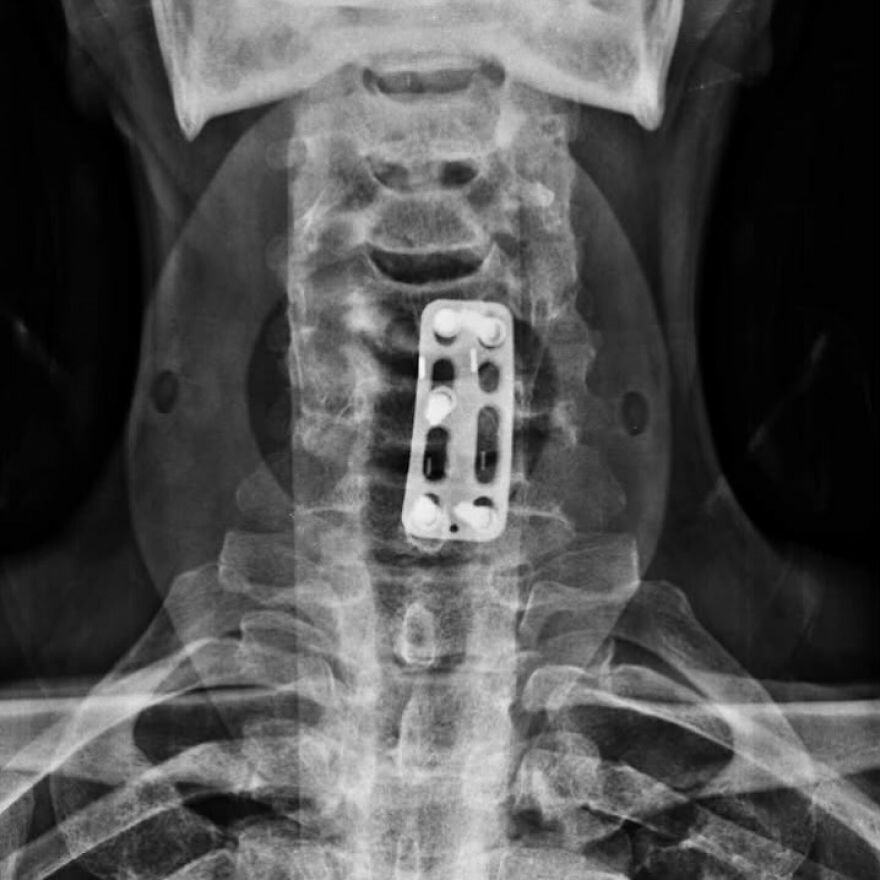

#8 Po prednej cervikálnej discektómii a fúzii (ACDF)